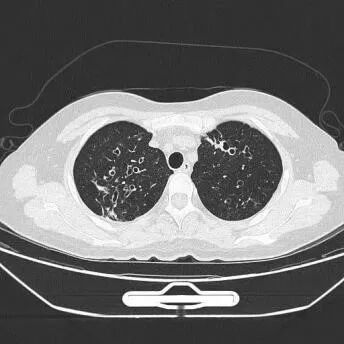

2.影像学检查:双肺支气管扩张并周边炎症

引起NTM肺病最常见的是脓肿分枝杆菌,好发于肺部已有基础疾病的患者,如慢性阻塞性肺疾病、支气管扩张症、囊性纤维化、尘肺病和肺泡蛋白沉着症等[6],常表现为慢性肺部疾病的恶化,也可有急性发病。脓肿分枝杆菌为条件致病菌,可通过皮肤、呼吸道等途径侵入人体,其病程与结核病相似,临床症状与肺结核亦相仿,如发热、盗汗、乏力、咳嗽、咯血等,胸部影像学表现也相似,其影像学以多发支气管扩张、薄壁空洞为特征性改变,同时伴有细支气管炎、多发微结节、树芽征及局部肺实变,仅仅依靠临床症状与胸部影像学表现容易误诊。

本案例为一例抗酸染色阳性结核分枝杆菌rpoB基因和突变检测阴性,患者出院后培养鉴定为脓肿分枝杆菌,微生物工作人员及时与该患者主管医生联系并与患者及时沟通进行下一步治疗的案例。该患者影像学报告显示双肺支气管扩张并周边炎症,长期咳嗽咳痰,患者曾就诊外地专科医院行培养后考虑诊断非结核分枝杆菌病,该病组织学上可分为四型:纤维空洞或类结核型、支气管扩张型、结节型及其他(肺纤维化、肺气肿、肺不张),结合以上类型考虑患者为支气管扩张性NTM。